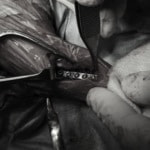

脊髄の減圧、脊柱管の再構築・安定化を目的に、片側椎弓切除術およびMatrixMANDIBLE Plateによる椎体固定を実施しました。

隣接椎体を架橋するようにプレートを設置しました。

Arthrex社のターゲティングデバイスを用いてピンニングの位置を調整することで、確実な固定を行っています。当院ではこの手術器具以外にも、人の手術にも使用される様々な器具を導入し、手術精度を高め、また医療メーカーと新しい器具の開発、試作にも取り組んでおります。